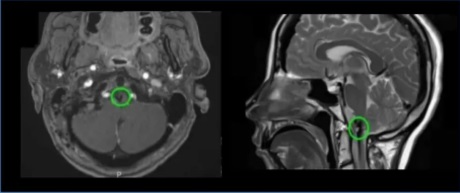

50岁女性-延髓海绵状血管瘤

28岁女性-脑干延髓海绵状血管瘤

19岁男孩-延髓海绵状血管瘤

32岁男性-延髓海绵状血管瘤

30岁女性-延髓-颈髓海绵状血管瘤